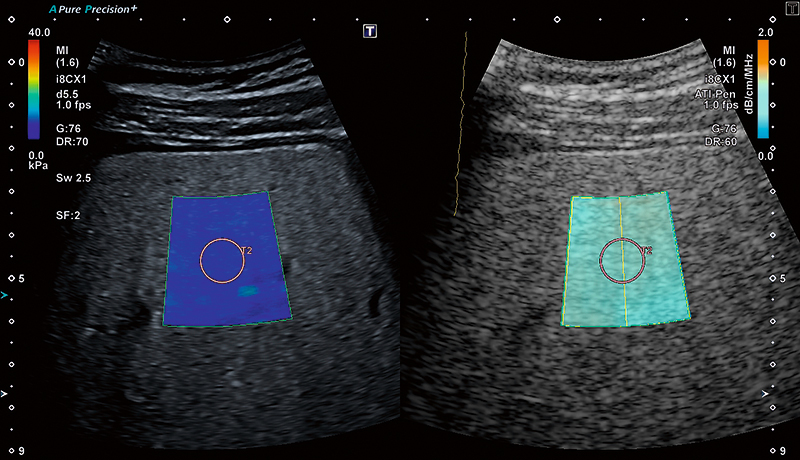

Візуалізація загасання (ATI) — це інноваційний інструмент, який може допомогти клініцистам в оцінці ступеня стеатозу. Рання характеристика наявного стеатозу є важливою як для надійного прогнозу, так і для ефективної терапії. ATI забезпечує кольорове кодування коефіцієнта загасання в тканинах печінки залежно від частоти.

ATI та SWE можна оцінювати одночасно за допомогою одного сканування. Завдяки цьому клініцисти можуть оцінити стеатоз печінки та фіброз ще швидше та ефективніше.